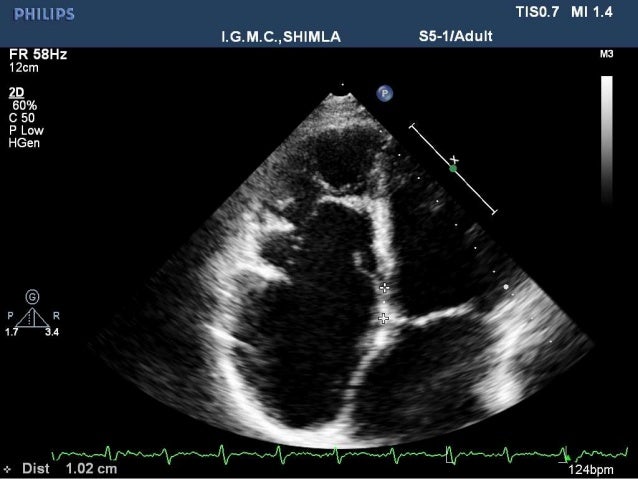

Apical 4 chamber view shows multiple trabeculations and deep recesses at the ventricular apex. Rarely, more than 3 prominent trabeculations that is the so-called LV noncompaction of ventricular myocardium (NVM) can be found at autopsy and by various imaging techniques including echocardiography and MRI etc. Eur Heart J.

Moderate to severely depressed left ventricular systolic function. Using 2-D echocardiography, less than 1% of patients are diagnosed with this entity. Heavily trabeculated left ventricle, most pronounced in the apical and left ventricular free wall.

Closer to the apex the noncompacted myocardium is more evident with trabeculations seen in the anterolateral wall and inferior wall. Left ventricular noncompaction (LVNC) is a distinct phenotype characterized by prominent LV trabeculae and deep intertrabecular recesses 1,2. NVM is recently included in the 06 classsification of cardiomyopathies as a Genetic Cardiomyopathy 3.